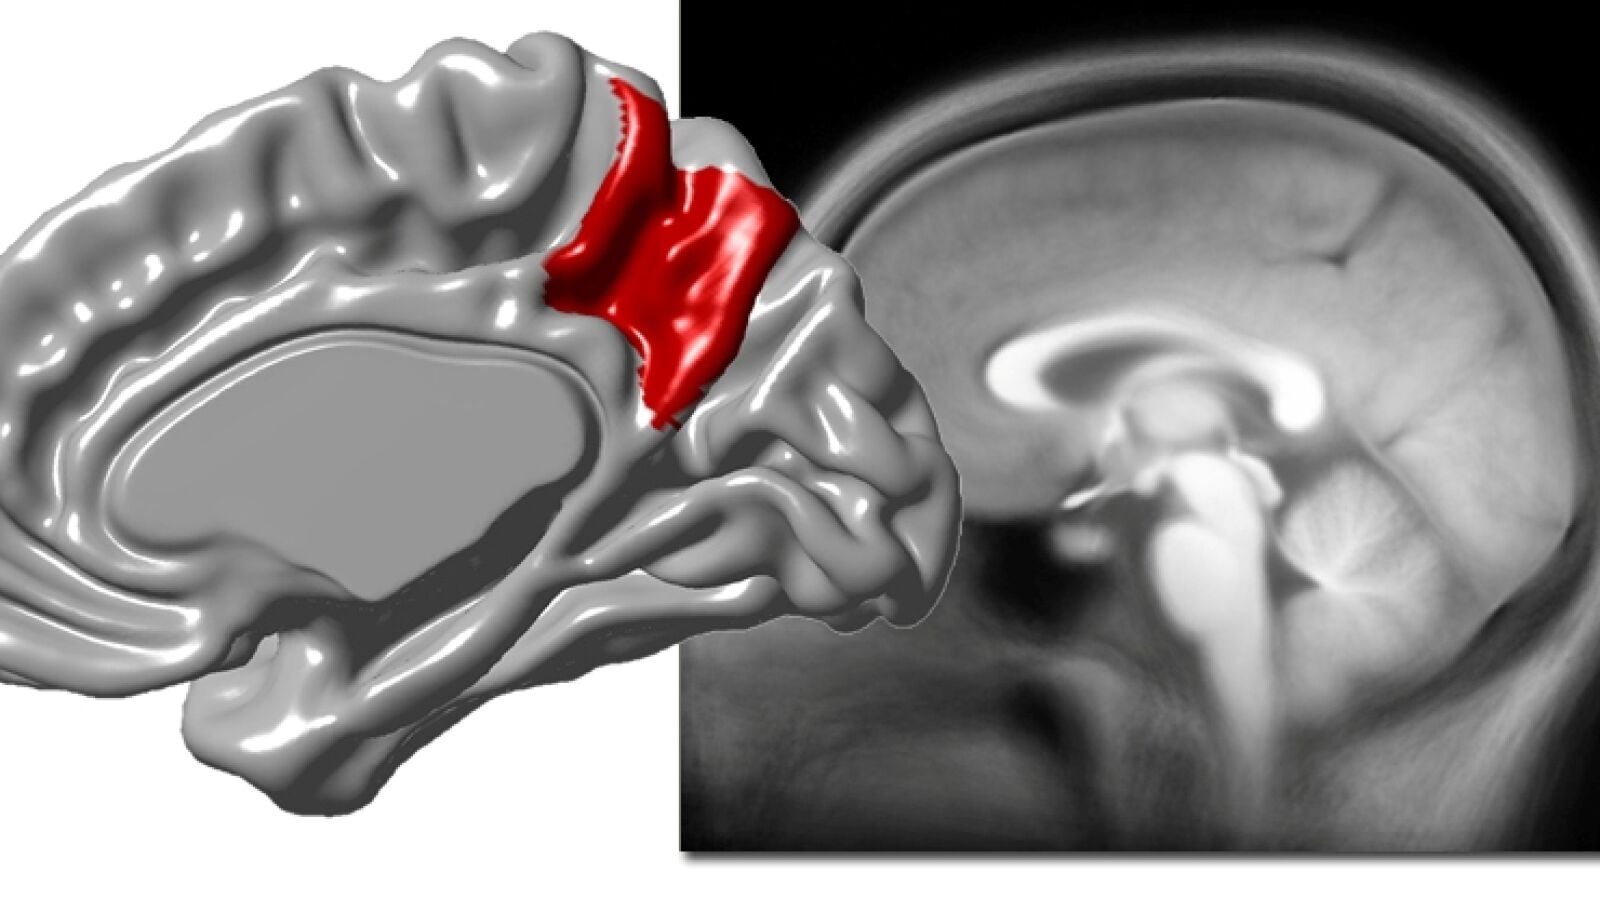

El paleoneurólogo Emiliano Bruner, investigador del Centro Nacional de Investigación del Centro Nacional de Investigación sobre la Evolución Humana (CENIEH) acaba de publicar en la revista Neuroscience, con la colaboración de la Universidad Autónoma de Madrid y de la Universidad Complutense de Madrid, un nuevo artículo sobre la neuroanatomía de las áreas parietales, en concreto sobre la superficie cortical del precúneo, cuyos resultados evidencian que su marcada variabilidad neuroanatómica entre los adultos se debe a un aumento de su volumen, y no solo a un cambio de sus proporciones.

En particular, se demuestra que las diferencias entre los individuos están asociadas a variaciones de la superficie de la corteza cerebral.

El precúneo ha recibido considerable atención en la última década, debido a sus funciones cognitivas, pero también a su participación en los procesos neurodegenerativos.

En estudios precedentes del mismo equipo habían evidenciado que las áreas parietales profundas podrían estar involucradas en la evolución del cerebro moderno, además de representar un rasgo extremadamente variable entre los adultos de nuestra especie, y de estar implicadas en etapas tempranas de la enfermedad de Alzheimer.